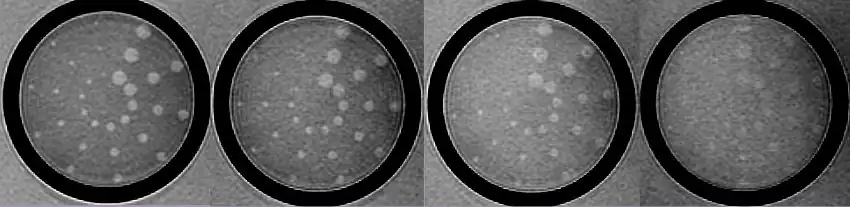

Contrast resolution is usually measured by generating a pattern from a test object that depicts how image contrast changes as the structures being imaged get smaller and closer together. The picture below shows one such set of images produced using the low contrast detectability inserts of the phantom employed in the MRI accreditation program of the American College of Radiology.